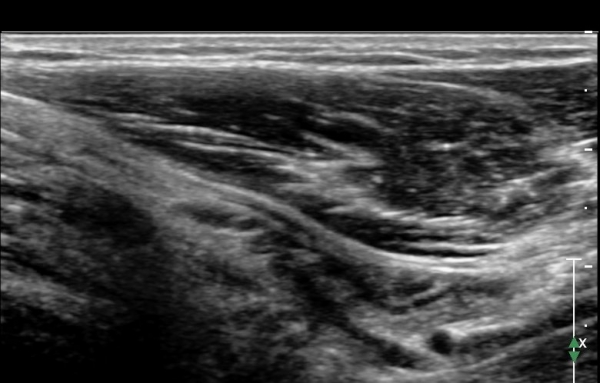

Á¤Á߽Űæ Á¾´Ü¸é°Ë»ç¿¡¼­ ȸ³»±Ù ¿ä°ñµÎ ±â½ÃºÎ¿¡¼­ Á¤Á߽ŰæÀÇ ±¹¼ÒÀû ¾Ð¹Ú°ú Ç¥ÃþÀ¸·Î ÀüÀ§°¡

°üÂûµÇ°í ¾Ð¹ÚÀÇ ±ÙÀ§ºÎ¿¡¼­´Â Á¤Áß½Å°æ ºÎÁ¾ÀÌ °üÂûµÊ(»çÁö 3).

ÀÌ·± º¯È­´Â °ÇÃø(»çÁø 6)°ú ºñ±³ÇÏ¸ç ¶Ñ·ÇÇÔ.